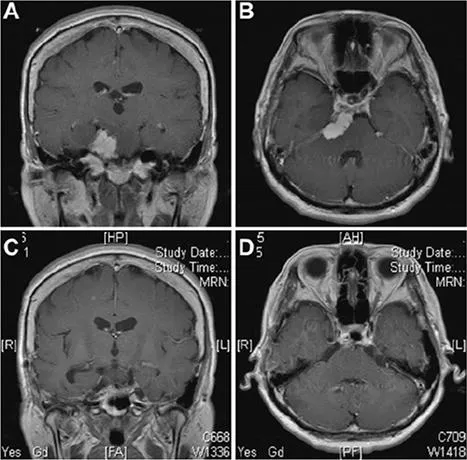

53岁女性,表现为悸动性头痛,并观察到左眼视力急剧下降。MRI显示一个均匀增强的肿块,集中在岩斜上交界处,广泛附着在上斜坡和天幕上(图A和B)。进行了Kawase入路。在滑车神经入幕附近行小脑幕切口后,可见三叉神经向双侧下移位,部分被肿瘤包裹,与上斜坡相连,部分钙化。外展神经在切除肿瘤后被观察到向下移位。MRI(图C和图D)显示肿瘤完全切除,无任何脑损伤。患者术后出现部分侧视麻痹,1个月后完全消失,恢复正常。

图示:术前图像(A和B)提示岩斜区一均匀强化的肿瘤,起源于岩尖,附着在小脑幕上。肿瘤推挤脑干,侵犯海绵窦。术后(C和D)显示肿瘤全切。